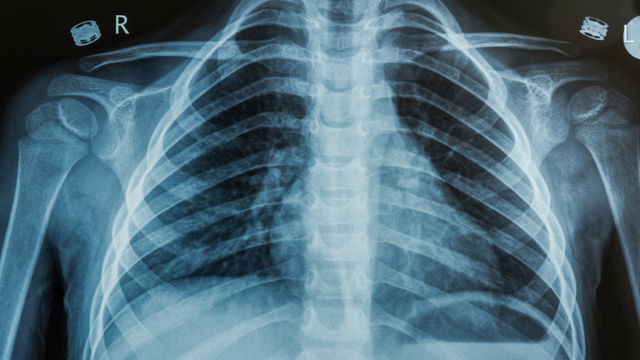

Gãy xương